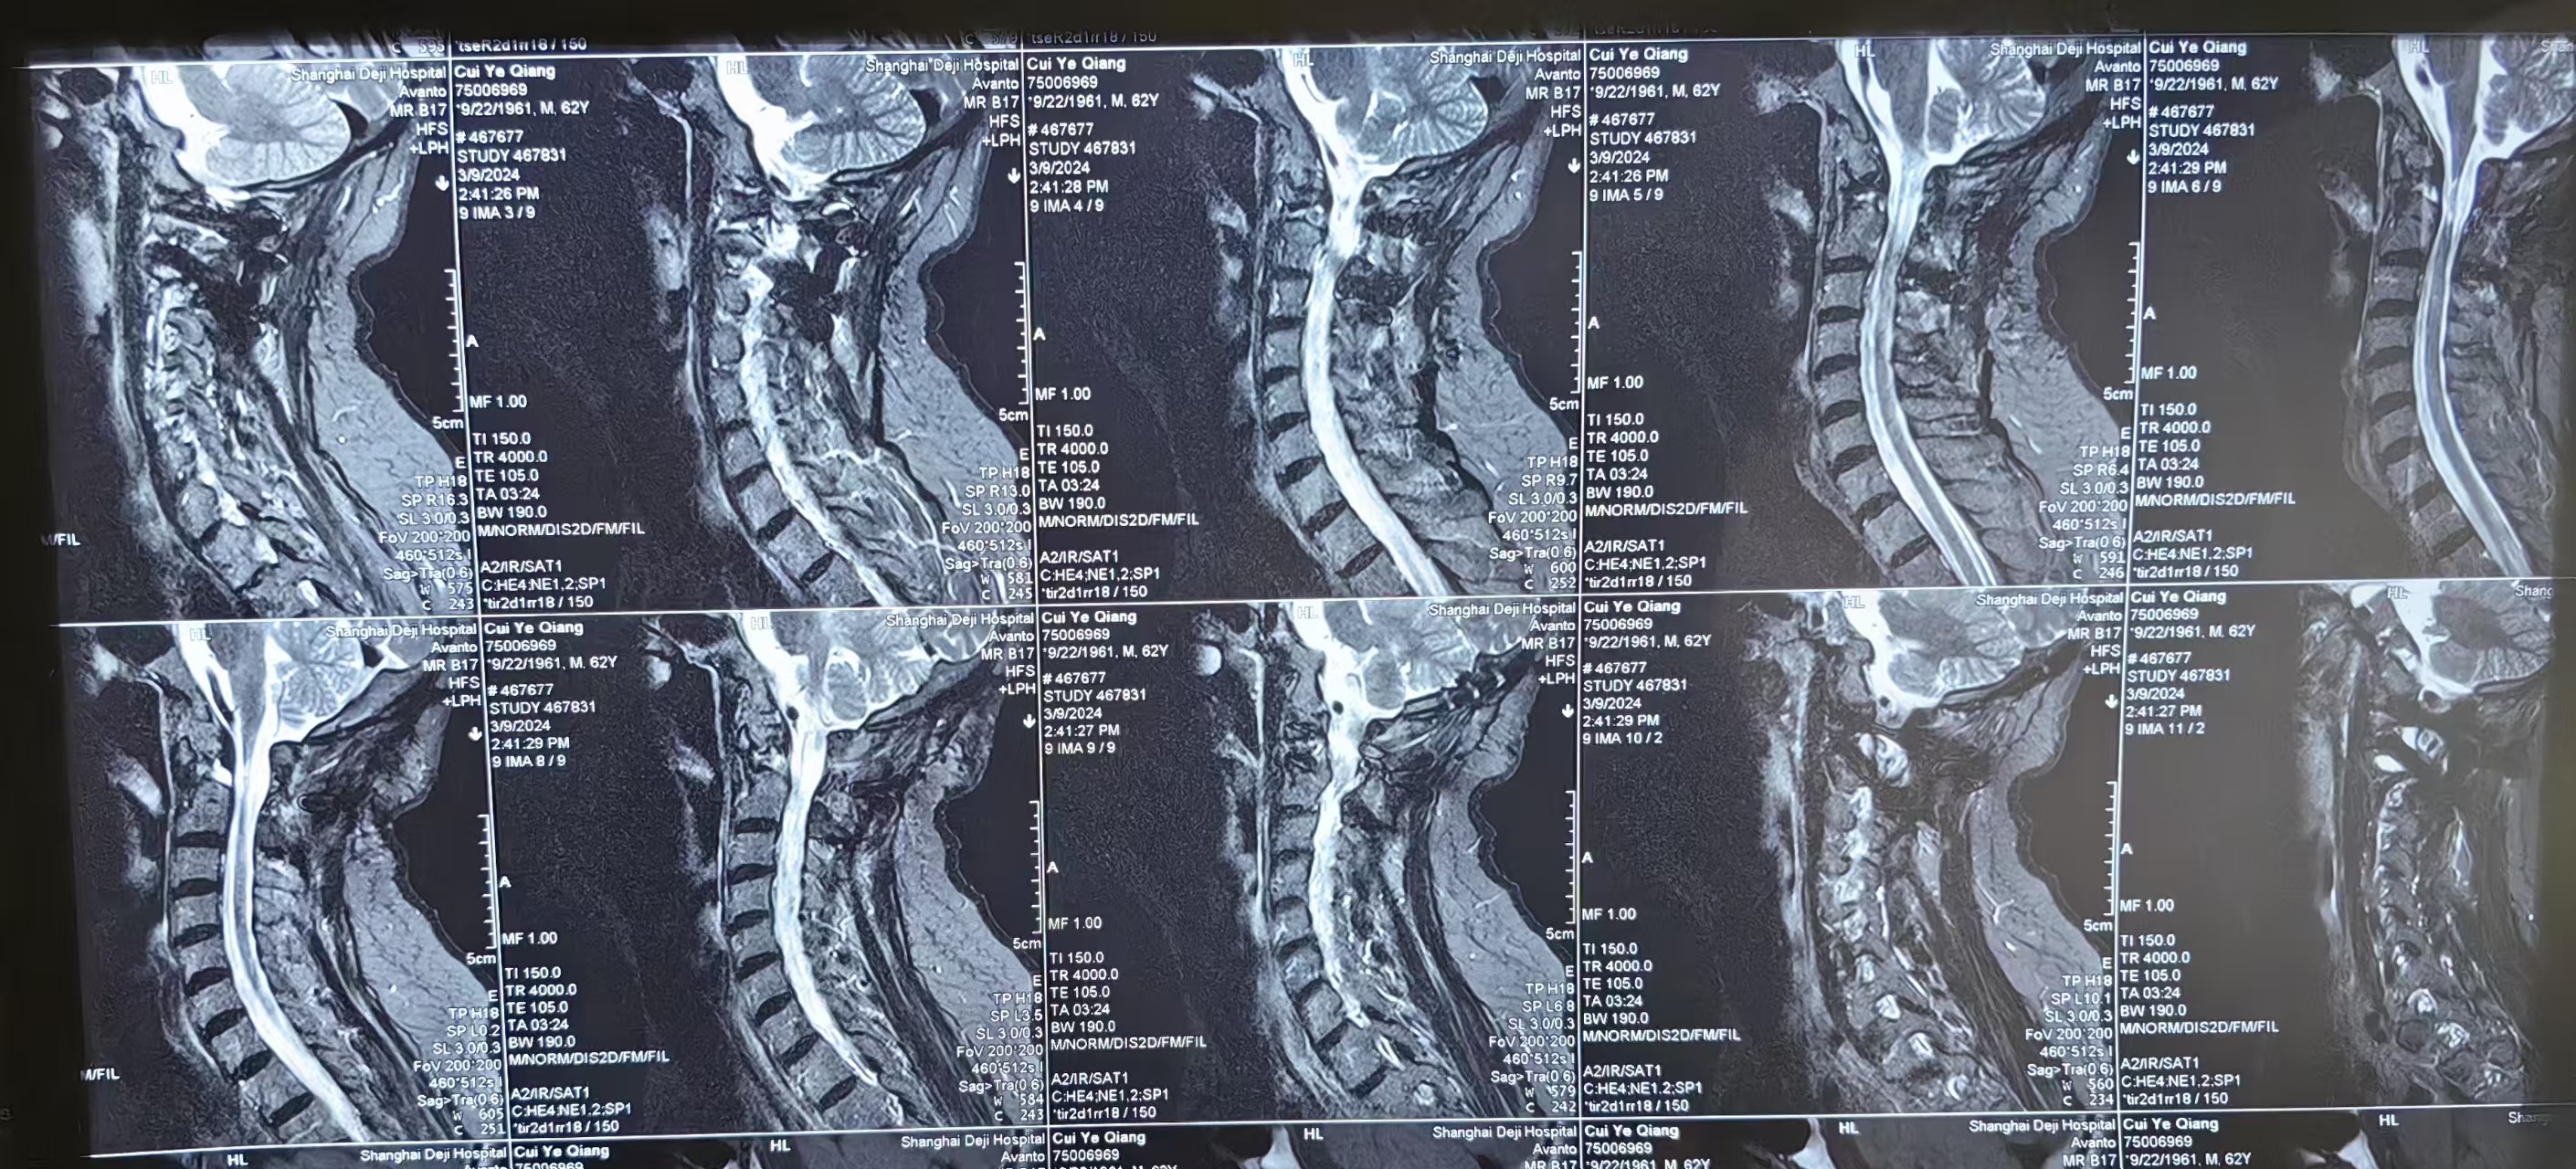

• 2024.03.09,复查,对位良好,但术前症状难以恢复。